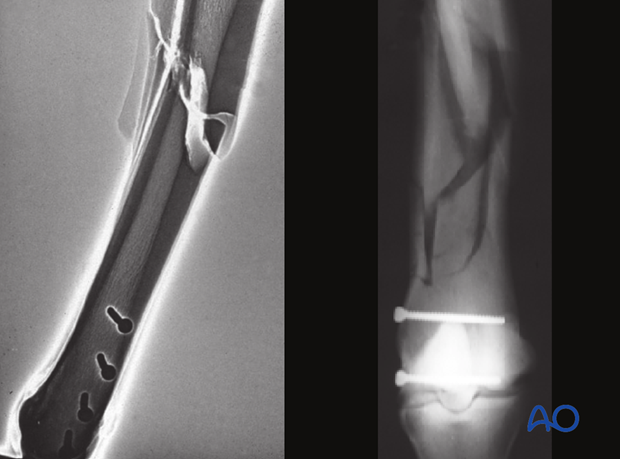

The major principle involved in standing lag screw fixation of these fractures is compression of the articular surface.The fixation of the distal portion of the bone may help prevent proximal propagation of the fracture, but definitely does not prevent it.

Standing lag screw fixation affords these benefits and specifically avoids the risks of recovery from general anesthesia. There remain risks for catastrophic failure for several weeks after fixation of the distal portion of the bone.

Although the glide hole is typically drilled through the smaller fragment and the thread hole across the larger fragment, this particular fracture is often repaired in the opposite manner. The major reason is that it is much safer and easier to approach the leg from the lateral side than the medial side. Fortunately, medial condylar fractures tend to be close to the midline so there is little difference between the width of the two fragments. The bone in this location is so strong that 25 mm of thread engaged with a 4.5 mm cortex screw is already exceeding the strength of the screw. Therefore, strong fixation can be achieved even though the repair is called “backward” or “reverse” lag screw.